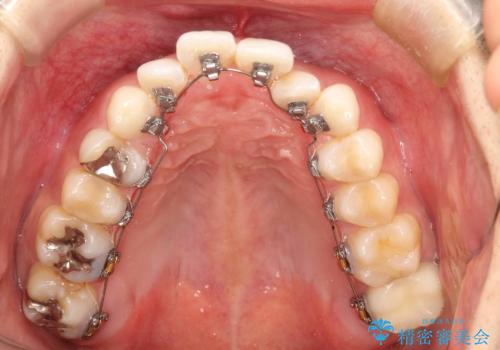

フルリンガル矯正 非抜歯でガタつきを整える

- フルリンガル

- フルリンガルワイヤーによる非抜歯治療を計画しました。